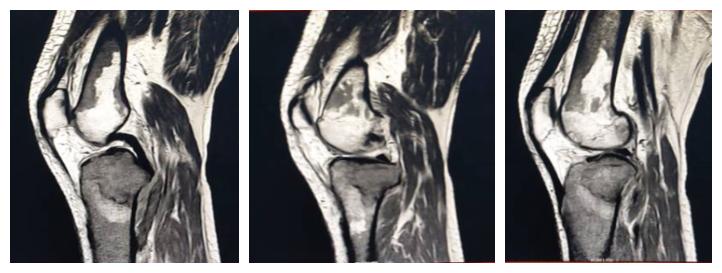

白血病关节病变:周某,男,71岁,既往白血病史,膝关节疼痛一月。

【eT1W-TSE SAG CLRAR】

影像所见:

脂肪抑制序列胫骨上端见片状高信号影,信号不均。

内、外侧半月板前后角形态及信号正常,边缘规整,前后交叉韧带、内外侧副韧带及髌韧带形态及信号未见异常。